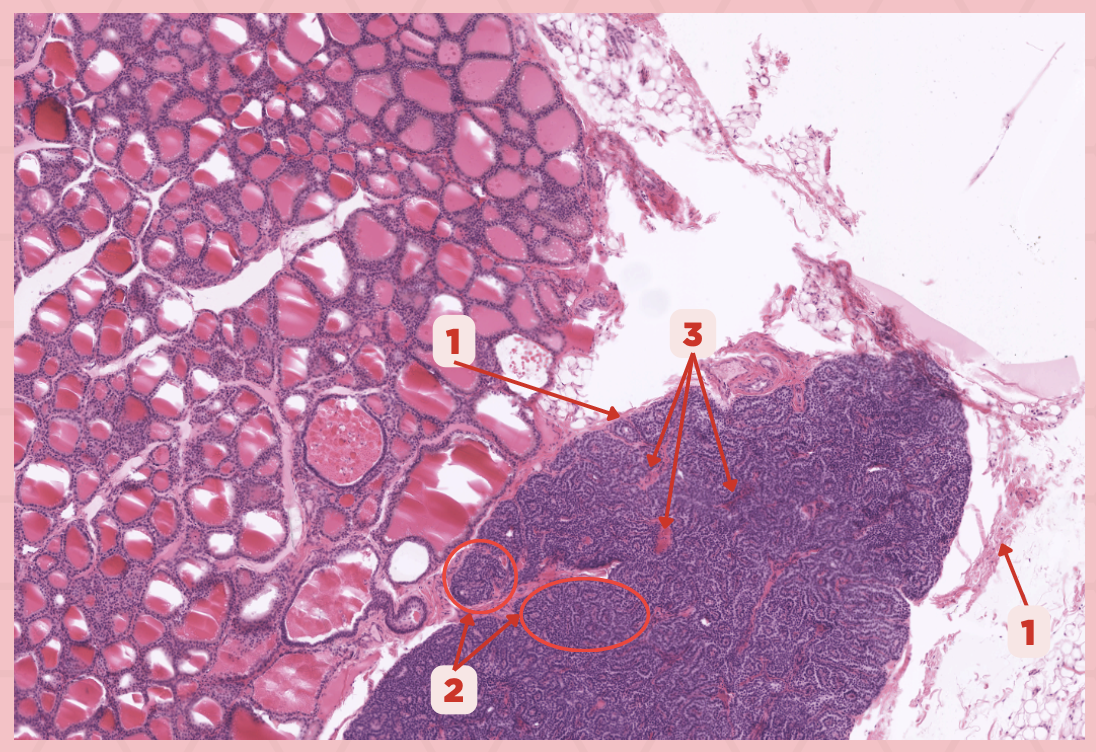

Parathyroid

Identify the specimen.

Chief Cells

Identify the structure labeled as 1. This comprise the majority of cells in the parathyroid gland.

Septa

Identify the structure labeled as 2.

Parathyroid hormones

What hormones are synthesized and secreted by the cell in Pointer #1?

Oxyphil cells

What parenchymal cells in the parathyroid gland only appear shortly before puberty and increase in number with age?